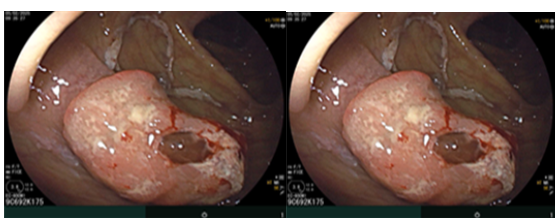

Sau đó bệnh nhân được nội soi dạ dày – đại tràng phát hiện đại tràng lên có khối lồi kích thước ~2.5cm, bề mặt nham nhở, cứng dễ chảy máu. Sinh thiết 03 mảnh. Giải phẫu bệnh: Ung thư biểu mô tuyến.

Hình 3. Tổn thương khối lồi xuất hiện ở vùng đại tràng lên

Nội soi đại tràng( thời điểm trước phẫu thuật T2/2025): Đại tràng lên có khối lồi kích thước ~ 2.5cm, bề mặt nham nhở, cứng dễ chảy máu.